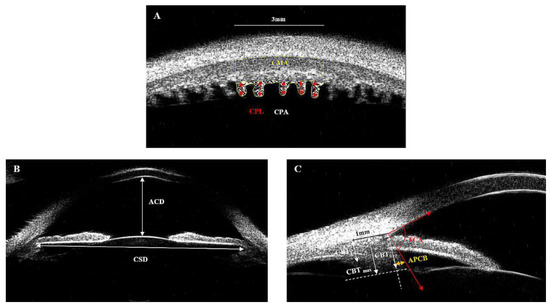

| CPL (mm) | 0.553 ± 0.069 | 0.555 ± 0.065 | 0.979(0.962,0.988) | <0.001 | −0.029, 0.024 | 44 |

| CPD (number) | 5.641 ± 0.669 | 5.660 ± 0.645 | 0.992(0.985,0.995) | <0.001 | −0.183, 0.147 | 44 |

| CPA (mm2) | 0.964 ± 0.127 | 0.962 ± 0.128 | 0.966(0.939,0.982) | <0.001 | −0.064, 0.066 | 44 |

| CMA (mm2) | 2.399 ± 0.288 | 2.368 ± 0.268 | 0.963(0.923,0.981) | <0.001 | −0.108, 0.169 | 44 |

| CBA (mm2) | 3.362 ± 0.291 | 3.333 ± 0.297 | 0.951(0.907,0.974) | <0.001 | −0.140, 0.203 | 44 |

| CPL (mm) | 0.513 ± 0.074 | 0.558 ± 0.070 | 0.490 ± 0.062 | 0.505 ± 0.075 | 0.498 ± 0.072 | <0.001 |

| CPD (number) | 5.779 ± 0.832 | 5.596 ± 0.702 | 5.752 ± 0.790 | 5.800 ± 0.937 | 5.969 ± 0.863 | 0.139 |

| CPA (mm2) | 0.890 ± 0.141 | 0.964 ± 0.130 | 0.841 ± 0.112 | 0.865 ± 0.142 | 0.889 ± 0.148 | <0.001 |

| CMA (mm2) | 2.381 ± 0.280 | 2.327 ± 0.312 | 2.483 ± 0.245 | 2.355 ± 0.270 | 2.361 ± 0.271 | 0.019 |

| CBA (mm2) | 3.271 ± 0.292 | 3.291 ± 0.328 | 3.323 ± 0.270 | 3.220 ± 0.282 | 3.250 ± 0.282 | 0.272 |

| CBT0 (mm) | 1.053 ± 0.188 | 1.014 ± 0.175 | 1.038 ± 0.142 | 1.054 ± 0.218 | 1.104 ± 0.203 | 0.084 |

| CBT1 (mm) | 0.811 ± 0.159 | 0.849 ± 0.181 | 0.789 ± 0.124 | 0.798 ± 0.147 | 0.811 ± 0.173 | 0.217 |

| CBTmax (mm) | 1.248 ± 0.169 | 1.224 ± 0.153 | 1.214 ± 0.152 | 1.261 ± 0.177 | 1.291 ± 0.183 | 0.064 |

| APCB (mm) | 0.349 ± 0.314 | 0.322 ± 0.144 | 0.324 ± 0.138 | 0.358 ± 0.235 | 0.392 ± 0.214 | 0.174 |

| TCA (degree) | 79.379 ± 10.020 | 77.859 ± 8.949 | 80.635 ± 8.587 | 80.583 ± 10.684 | 78.437 ± 11.531 | 0.343 |